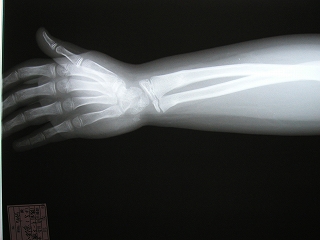

‰E‘O˜rœœÜ

@@”N—î@@8Î@—«

@@•‰“ú@•½¬14”N7ŒŽ27“ú

œÜÇ—á